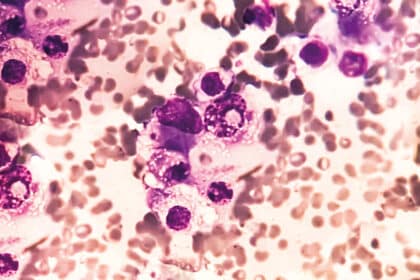

Multiples Myelom: Vorsicht bei unklaren Schmerzen